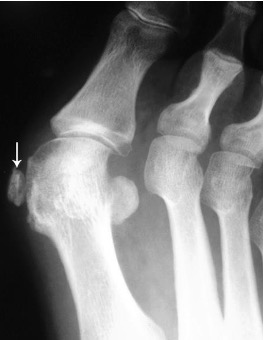

Gout

- Hyperuricaemia causes deposition of urate crystals

- First metatarso-phalangeal joint is commonly involved, termed a podagra

- Well-defined erosions with sclerotic borders which have a ‘punched out’ or ‘rat bite’ appearance and overhanging margin

- Joint space and bone density are preserved until late in the course of the disease

- Urate crystals deposited in the soft tissues form tophi and periarticular lobulated soft tissue masses

- Chondrocalcinosis may represent deposition of calcium pyrophosphate dihydrate (CPPD) crystals (pseudogout)

Gout of first MTP joint with well defined ‘punched out’ erosion with overhanging margin (arrow) and soft tissue swelling (arrowheads)